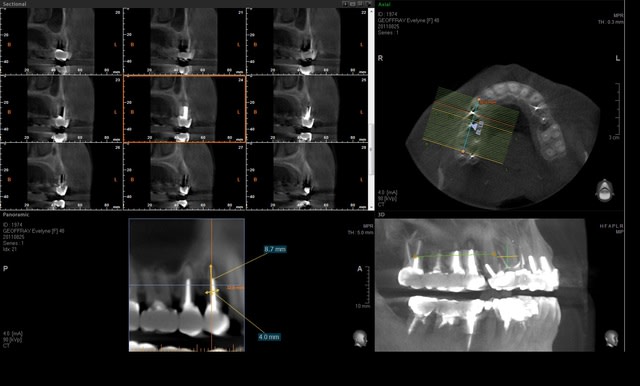

un cas de lundi.

Fracture verticale datant de 4 jours, avec un petit granulome circonscrit apical

Extraction, curetage du granulome

Mise en place d'un 4.20 X 11.5 torque au dessus de 25N

L'implant rentre d'environ 0.5 - 1mm dans le sinus...

Difficulté, arriver a placer l'implant dans l'espace radiculaire sans dévier.

J'ai dans mon kit un foret pointu (genre Stabyl) qui permet d'amorcer le forage dans des axes délicat, notamment les septum.

L'implant est bloqué par la parti apicale plus longue que la racine, et en mésio distal... il reste un espace vestibulo palatin comblé par le caillot.

Mise en esthétique immédiate....

Le nombre d'indication est quand même très rare...